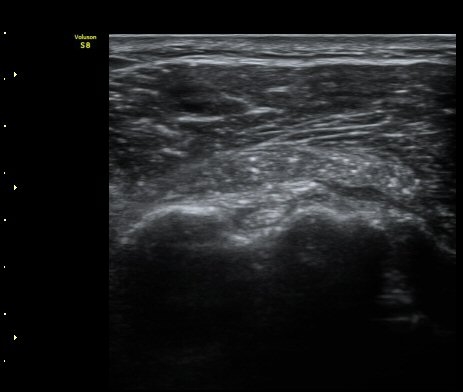

À̵ιڱ٠Á¾´Ü¸é°Ë»ç¿¡¼­µµ Á¡¾×³¶³» ¼®È­È­ À½¿µÀÌ °üÂûµÊ(±×¸² 4).

ÁÖ»ç ÈíÀΰú Á¡¾×³¶³» ÁÖ»çÄ¡·á(÷ºÎ ÆÄÀÏ) 1ÀÏ ÈÄ ½ÃÇàÇÑ °Ë»ç¿¡¼­ Á¡¾×³¶ÀÇ ºÎÁ¾ ¹× ¼®È¸ÀÇ

Á¦°Å°¡ °üÂû µÊ(±×¸² 6, 7).